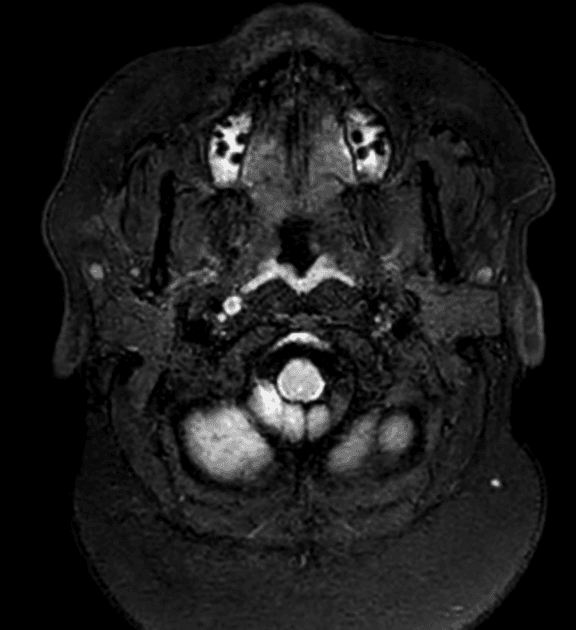

- Ghi nhận nhiều tổn thương kích thước thay đổi, ở hai bên tại vùng quanh não thất (periventricular), vùng cận vỏ (juxtacortical), vùng tiểu não, chi sau bên trái của bao trong (left posterior limb of the internal capsule) và cánh cầu bên trái (left brachium pontis).

- Các tổn thương vùng quanh não thất định hướng vuông góc với não thất (Dawson fingers).

- Các tổn thương biểu hiện tín hiệu giảm trên T1, tăng tín hiệu trên T2 và FLAIR.

- Một số tổn thương cho thấy hiện tượng T2 shine-through (tín hiệu tăng trên DWI và ADC tăng), trong khi một số khác, chủ yếu là các tổn thương quanh não thất, biểu hiện tín hiệu sáng dạng viền trên DWI với ADC ngoại vi giảm (hạn chế khuếch tán thật sự – true restriction).

- SWI phát hiện dấu hiệu tĩnh mạch trung tâm (central vein sign) tại tổn thương ở chi sau của bao trong (PLIC).